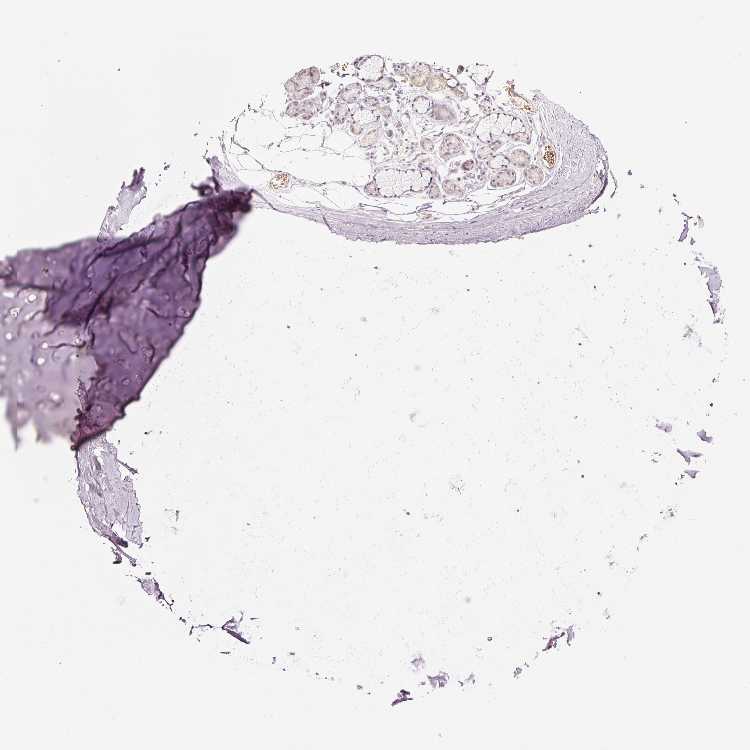

SOFT TISSUE 1 - Antibody stainingi

Antibody staining in the annotated cell types in the current human tissue is reported as not detected, low, medium, or high, based on conventional immunohistochemistry profiling in selected tissues. This score is based on the combination of the staining intensity and fraction of stained cells.

Each image is clickable and will lead to virtual microscopy that enables deeper exploration of all samples and also displays staining intensity scores, fraction scores and subcellular localization as well as patient and tissue information for each sample.

Antibody HPA053962

Chondrocytes Not detected

Fibroblasts Not detected

Peripheral nerve Not detected